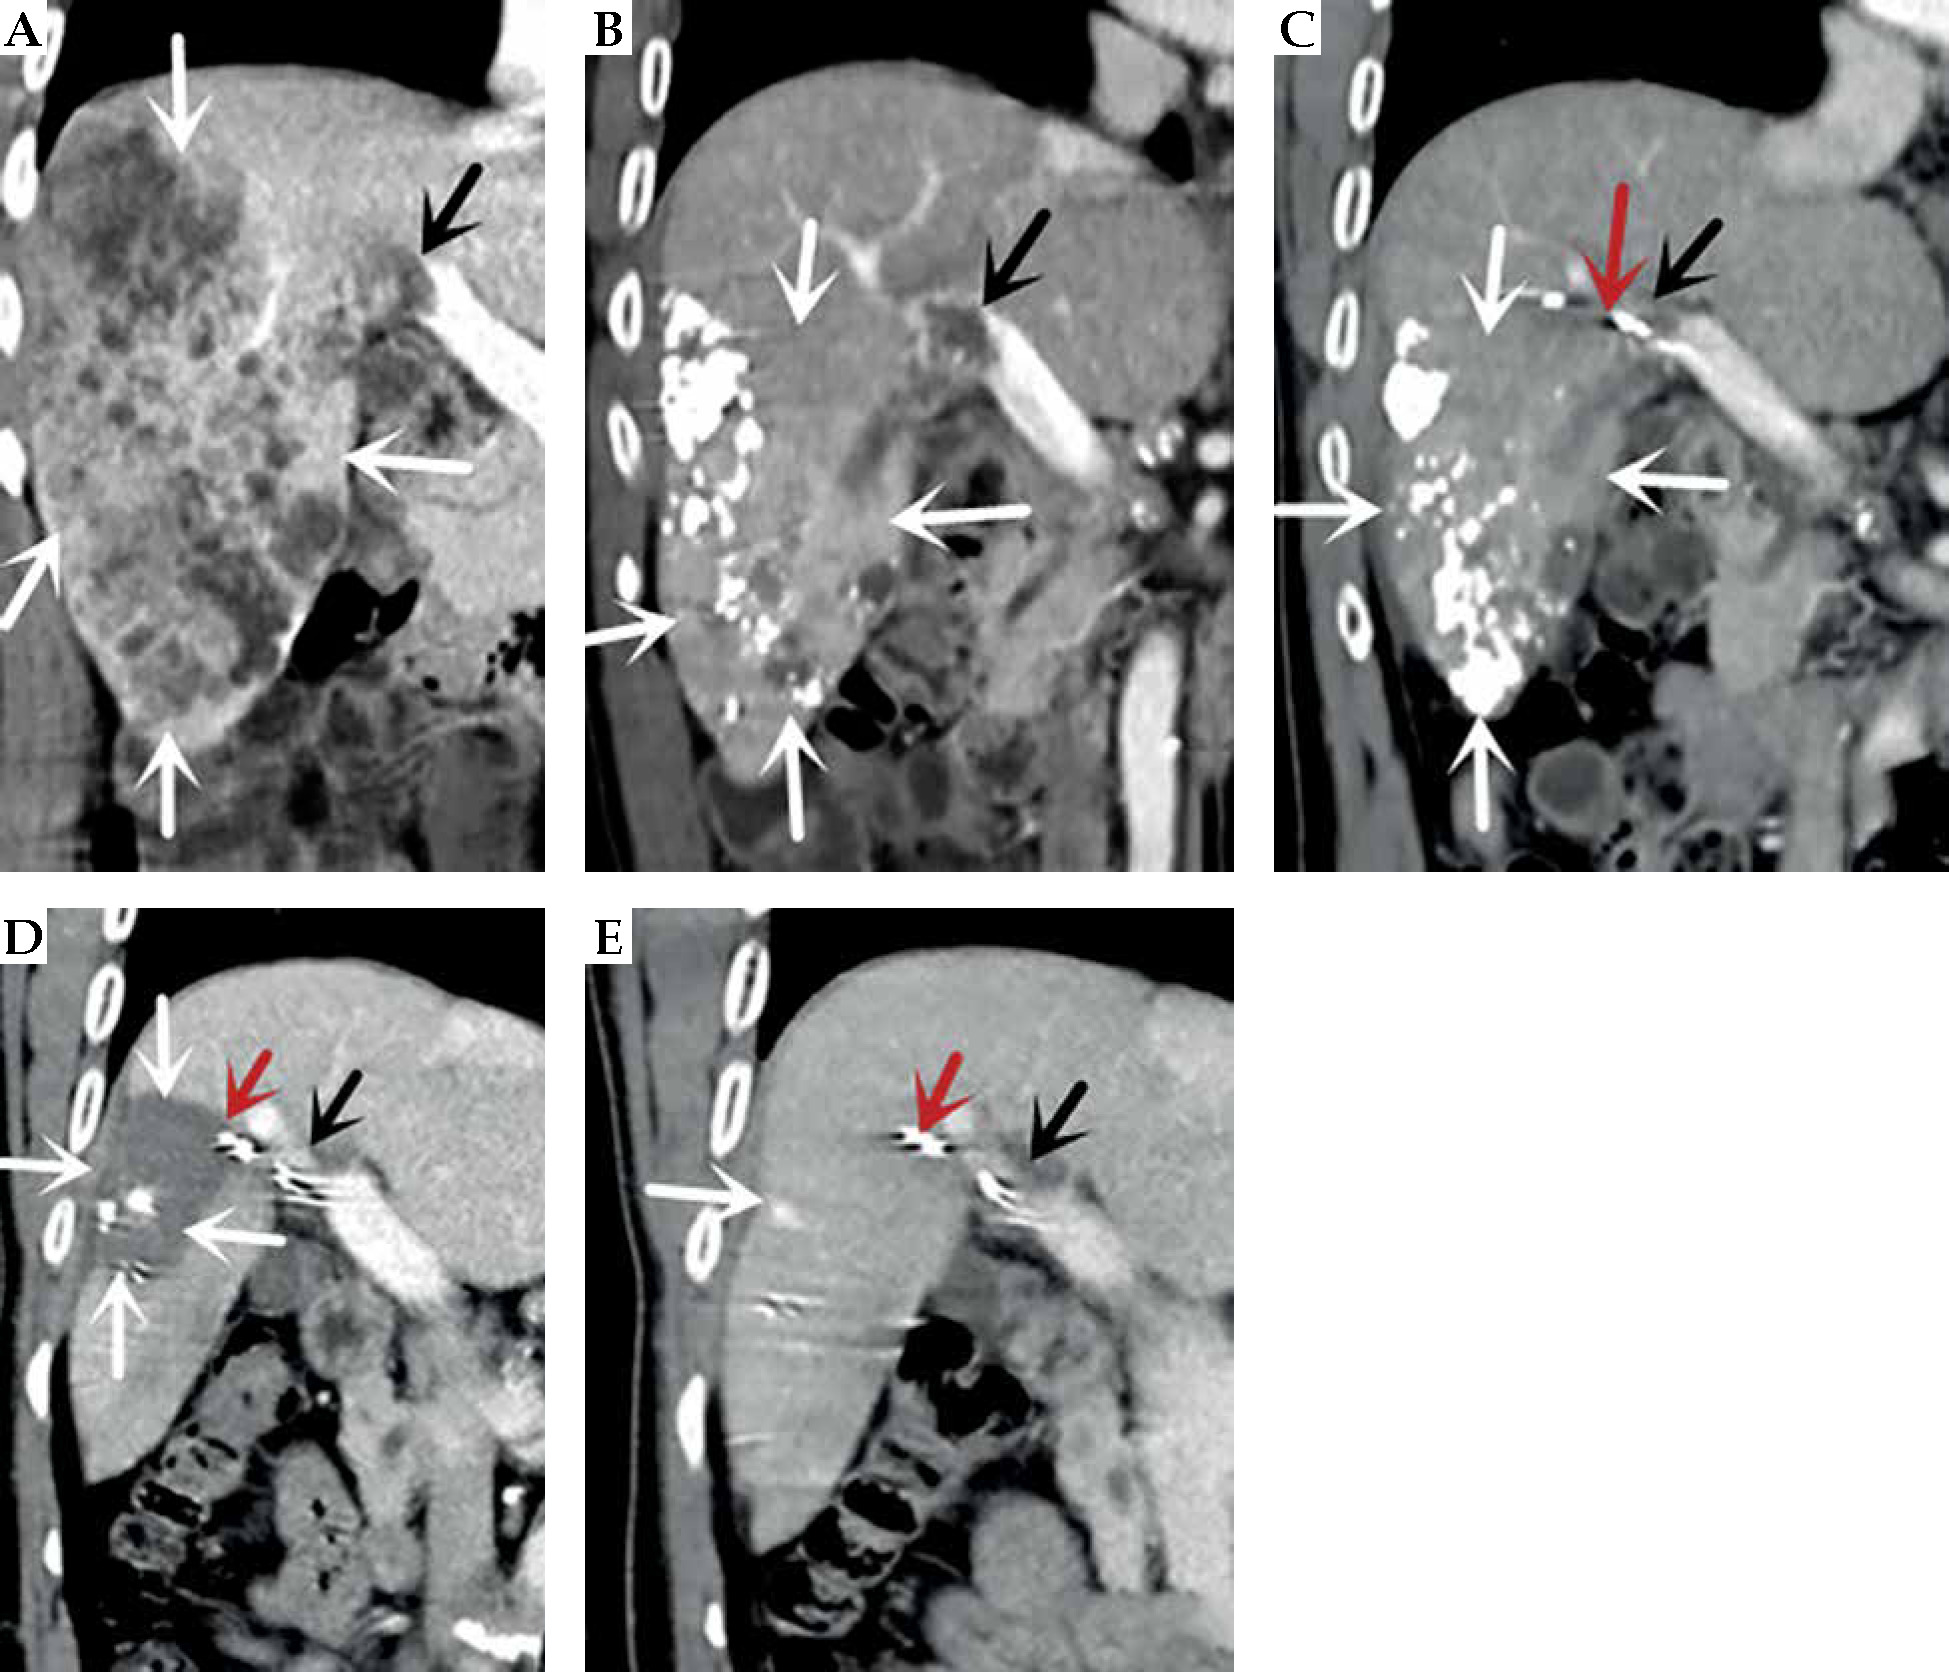

Fig. 3

Computed tomography (CT)-enhanced coronal images of portal phase before and after treatment. A) Before treatment. B) After more than 1 month of treatment. C) After more than 8 months of treatment. D) After more than 15 months of treatment. E) After more than 23 months of treatment. The white arrow indicate the liver cancer lesion, which is gradually shrinking, the black arrow is the portal cancer thrombus, which is gradually shrinking and disappearing, and the portal vein is partially open, the red arrow is the radioactive 125I particle